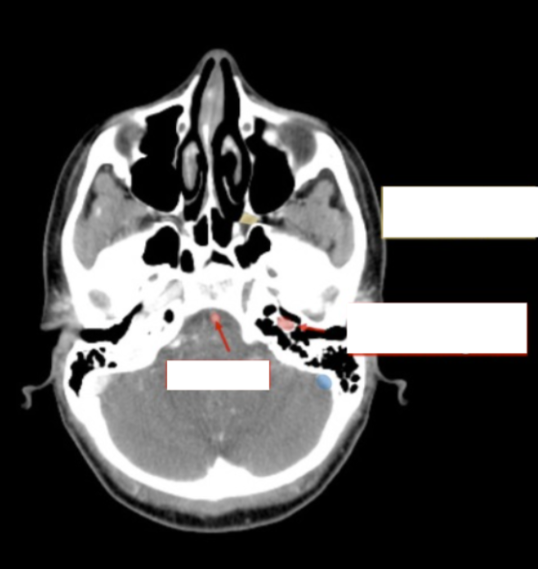

Please label